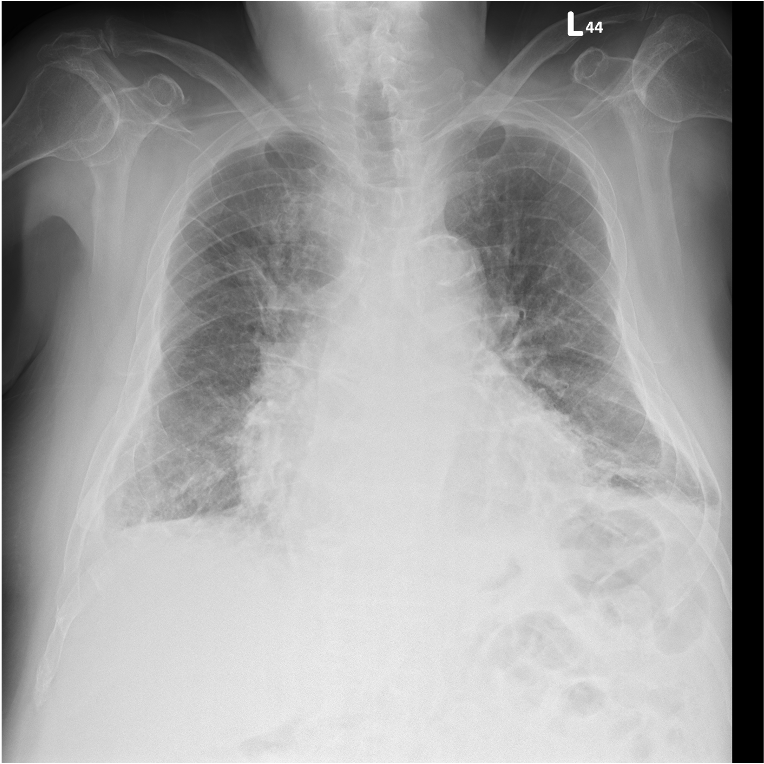

Echocardiography revealed LVEF 32% with severe functional mitral regurgitation, LVEDD 61 mm, and RV dysfunction (TAPSE 1.4 cm). BNP was 6421 pg/mL. Chest X-ray showed pulmonary congestion and cardiomegaly. ECG demonstrated sinus tachycardia with Q waves over anterior leads. Renal and hepatic profiles were mildly impaired, and NT-proBNP remained elevated despite guideline-directed medical therapy.